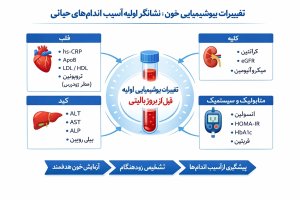

نشانگرهای بیوشیمیایی مرتبط با آسیب زودهنگام اندامهای حیاتی

۱. کبد؛ آسیب خاموش اما قابلتشخیص

- افزایش ALT و AST (حتی خفیف)

- بالا رفتن GGT

- تریگلیسرید بالا

- نسبت غیرطبیعی AST/ALT

این الگوها میتوانند نشانه اولیه کبد چرب غیرالکلی، التهاب کبد یا استرس متابولیک باشند.

۲. کلیهها؛ افت عملکرد پیش از علائم

- افزایش کراتینین سرم (حتی لب مرز)

- کاهش eGFR

- افزایش اوره خون

- وجود آلبومین در ادرار (میکروآلبومینوری)

۳. قلب و عروق؛ هشدارهای زودهنگام در خون

- LDL بالا یا HDL پایین

- تریگلیسرید بالا

- افزایش hs-CRP (التهاب عروقی)

- افزایش خفیف تروپونین در شرایط خاص

۴. پانکراس و اختلالات قند خون

- قند خون ناشتا بالا

- HbA1c لب مرز

- انسولین ناشتا بالا (مقاومت به انسولین)

- تریگلیسرید بالا